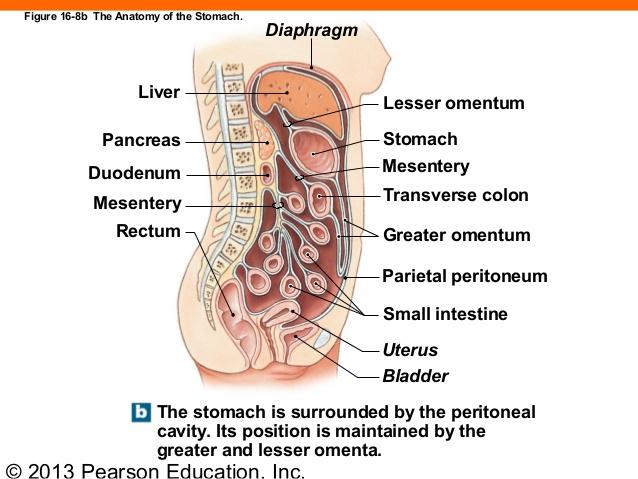

Serous membranes

...

2

Parietal Peritoneum

3

Dorsal Mesentery

4

Visceral Peritoneum

5

Lesser Omentum

6

Greater Omentum